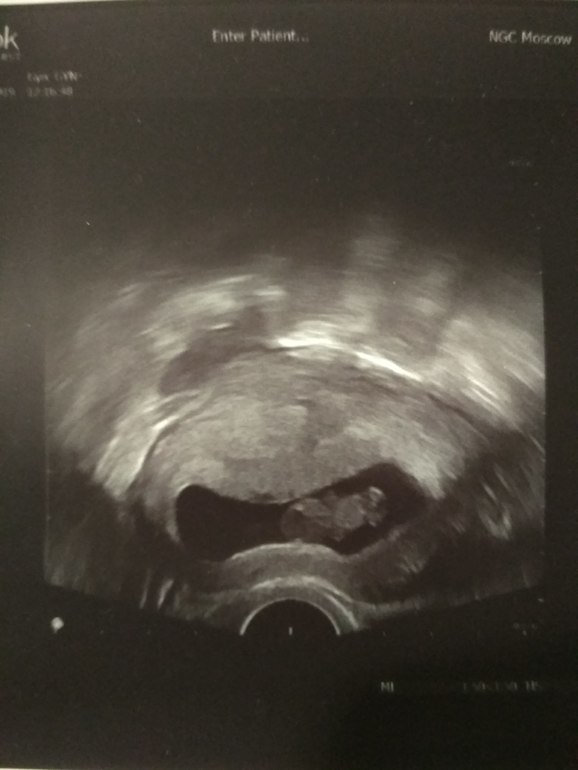

Контрольное УЗИ!)

Поздравляю! Чудесное фото! Здоровья Вам и доченьке!)

Маленький человечек))) Растите, легкой вам беременности!